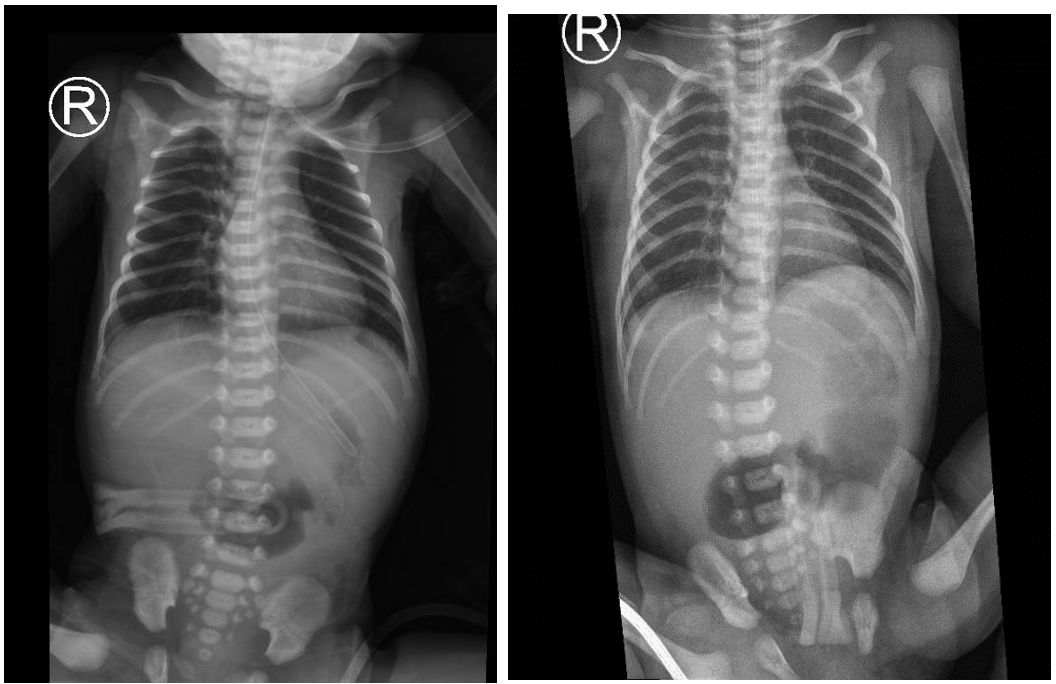

External genitalia and anal opening were normal. The baby has passed only pale mucus per rectum. Plain abdominal X-ray demonstrated the classic “double bubble” sign with absence of distal bowel gas (Figure 1).

Figure 1: Plain abdominal x-ray showing double-bubble sign with no gas distally.

Clinically, neonates typically present with bilious vomiting soon after birth and antenatal polyhydramnios [6], consistent with our patient’s presentation. Radiologically, the “double bubble” sign is suggestive of duodenal atresia, but distal bowel pathology such as apple-peel atresia is diagnosed intraoperatively.